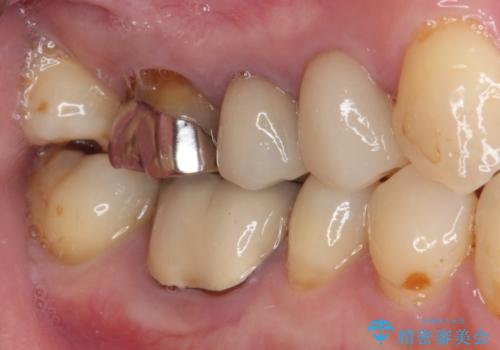

- 下顎の奥歯に頻繁に物が挟まるとのことで来院された患者様です。

最近ものが挟まりやすくなったり、冷たいものがしみるようになったりといった症状があり、診査したところ、歯質の欠損や不適修復物などが認められました。

精度の高いセラミックインレーによる修復治療を行うこととしました。